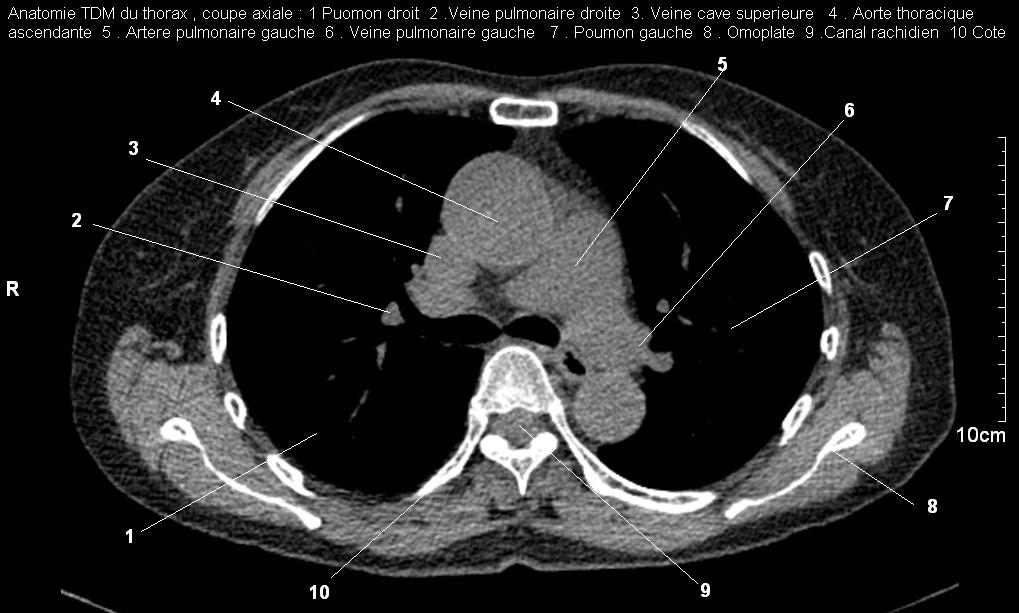

Image radiologique TDM normal

, coupe axiale , fenetre parenchymateuse du

bronchous droit et gauche . Le bronchus droit

est en aspect arrondie hypodense très nette ,

bronchous gauche ovalaire , lisse , nette très

hypodensite de vide en avant , pres de os vertebral

TH3-4 . (

click pour entrer ) |